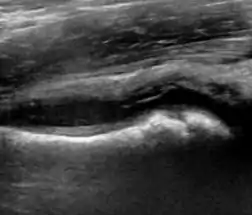

During childhood, ultrasound is a quick method to assess hip pain and quite often may be used to avoid use of irradiating techniques, such as radiography or CT. Ultrasound allows evaluation of joint effusion, synovial thickening and neovascularity, the bone/cartilage contour, and the femoral head-neck alignment. Although sonography is extremely sensitive in detecting increased synovial fluid, it is nonspecific and cannot be used with accuracy to determine the type of fluid. Transient synovitis of the hip, despite being the most frequent cause of pain in children between 3 and 10 years, remains a diagnosis of exclusion. It usually shows anechoic fluid, but echogenic fluid can also be found. The effusion is considered pathologic when it is measured at >2 mm in thickness. The differential diagnosis is wide, including osteomyelitis, septic arthritis, primary or metastatic lesions, LCPD, and SCFE. Discrimination from septic arthritis is challenging, often requiring joint aspiration. In septic arthritis, US is able to demonstrate a hip joint effusion, synovial thickening, and cartilage damage, although the appearances are nonspecific.[1]

A step between the head and the physis can be detected in children with SCFE, while abnormalities in the femoral head contour may suggest the presence of LCPD. In both cases, radiographs are mandatory to confirm diagnosis and severity (Figure 12).[1]

Figure 12:

Normal ultrasound appearance of the femoral head-neck junction.

Joint effusion in transient synovitis of the hip.

Flattening of the femoral head in a patient with Perthes disease.

Step in the femoral head-neck junction in a patient with SCFE.